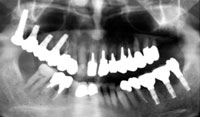

パノラマレントゲン写真

吉本歯科医院では、口内写真とパノラマレントゲンを撮影し、まずは顎の骨の状態まで詳しく確認しました。

CT画像で見ると骨の厚みが1、2ミリしかなく、通常の10ミリのインプラントを入れればシミュレーションのように鼻の空洞に突き抜けてしまうばかりでなく、強い力で噛んだ時に骨折する恐れがあります。.